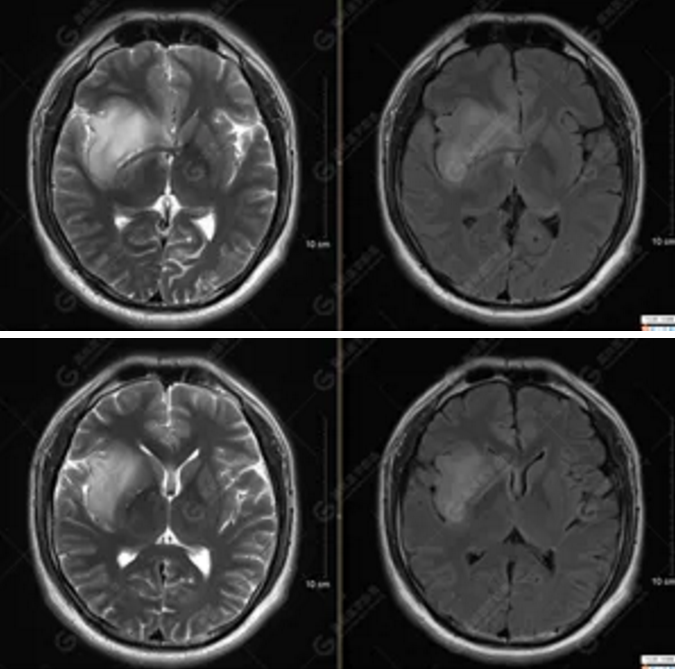

【MRI平掃及增強(qiáng)檢查所見(jiàn)】右側(cè)額顳島葉、右側(cè)海馬及右側(cè)基底節(jié)區(qū)見(jiàn)一團(tuán)塊狀異常信號(hào)影,累及右側(cè)下丘腦及視交叉,大小約5.1cm×4.5cm×4.3cm,呈長(zhǎng)T1長(zhǎng)T2信號(hào),F(xiàn)LAIR序列呈等、稍高信號(hào),DWI序列呈稍高信號(hào),ADC圖高信號(hào),增強(qiáng)后無(wú)明顯強(qiáng)化;病灶周?chē)?jiàn)片狀長(zhǎng)T1長(zhǎng)T2水腫信號(hào)影,F(xiàn)LAIR序列呈高信號(hào),病灶內(nèi)見(jiàn)右側(cè)大腦中動(dòng)脈穿行。余腦實(shí)質(zhì)內(nèi)未見(jiàn)局灶性信號(hào)異常,增強(qiáng)后未見(jiàn)異常強(qiáng)化。右側(cè)側(cè)腦室輕度受壓,余腦室、腦池大小、形態(tài)均正常,中線(xiàn)結(jié)構(gòu)居中

以上為DTI成像,圖1為皮質(zhì)脊髓束,圖2為胼胝體束,圖3為扣帶回束,圖4為額枕束。DTI成像示右側(cè)額枕束前部明顯受壓、部分未見(jiàn)顯示;胼胝體束、雙側(cè)扣帶束、皮質(zhì)脊髓束及左側(cè)額枕束形態(tài)可,纖維束未見(jiàn)明顯破壞,未見(jiàn)明顯稀疏減少。